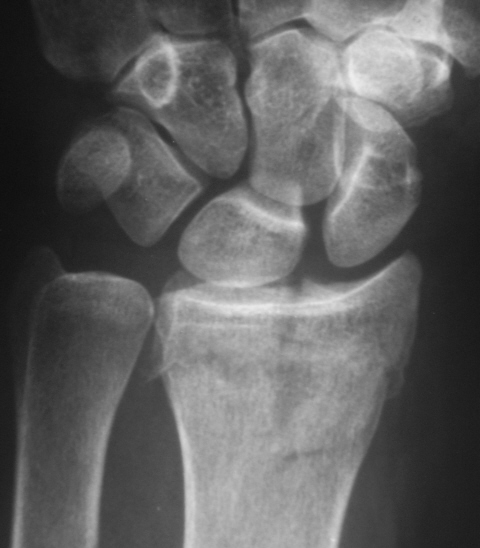

Случай 1. Пациент направлен хирургом на рентгенографию лучезапястного сустава.